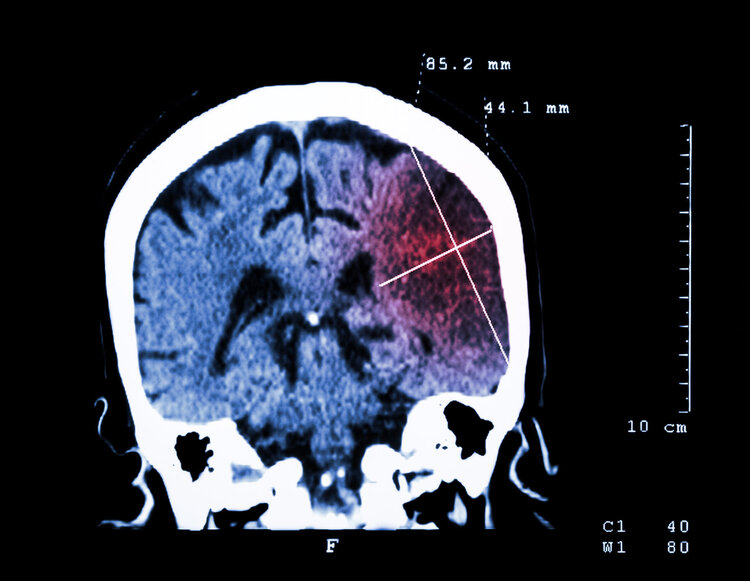

家人紧急将他送往医院,到达医院时他整个人的意识十分模糊,医生初步判断是 脑梗 所致。随后,医生为其进行了 手术取栓。

医生介绍,房颤患者容易在心房内形成血栓,这种血栓黏附不牢,会随着血液流动“乱跑”,当流至脑内大血管时,就会导致脑梗。